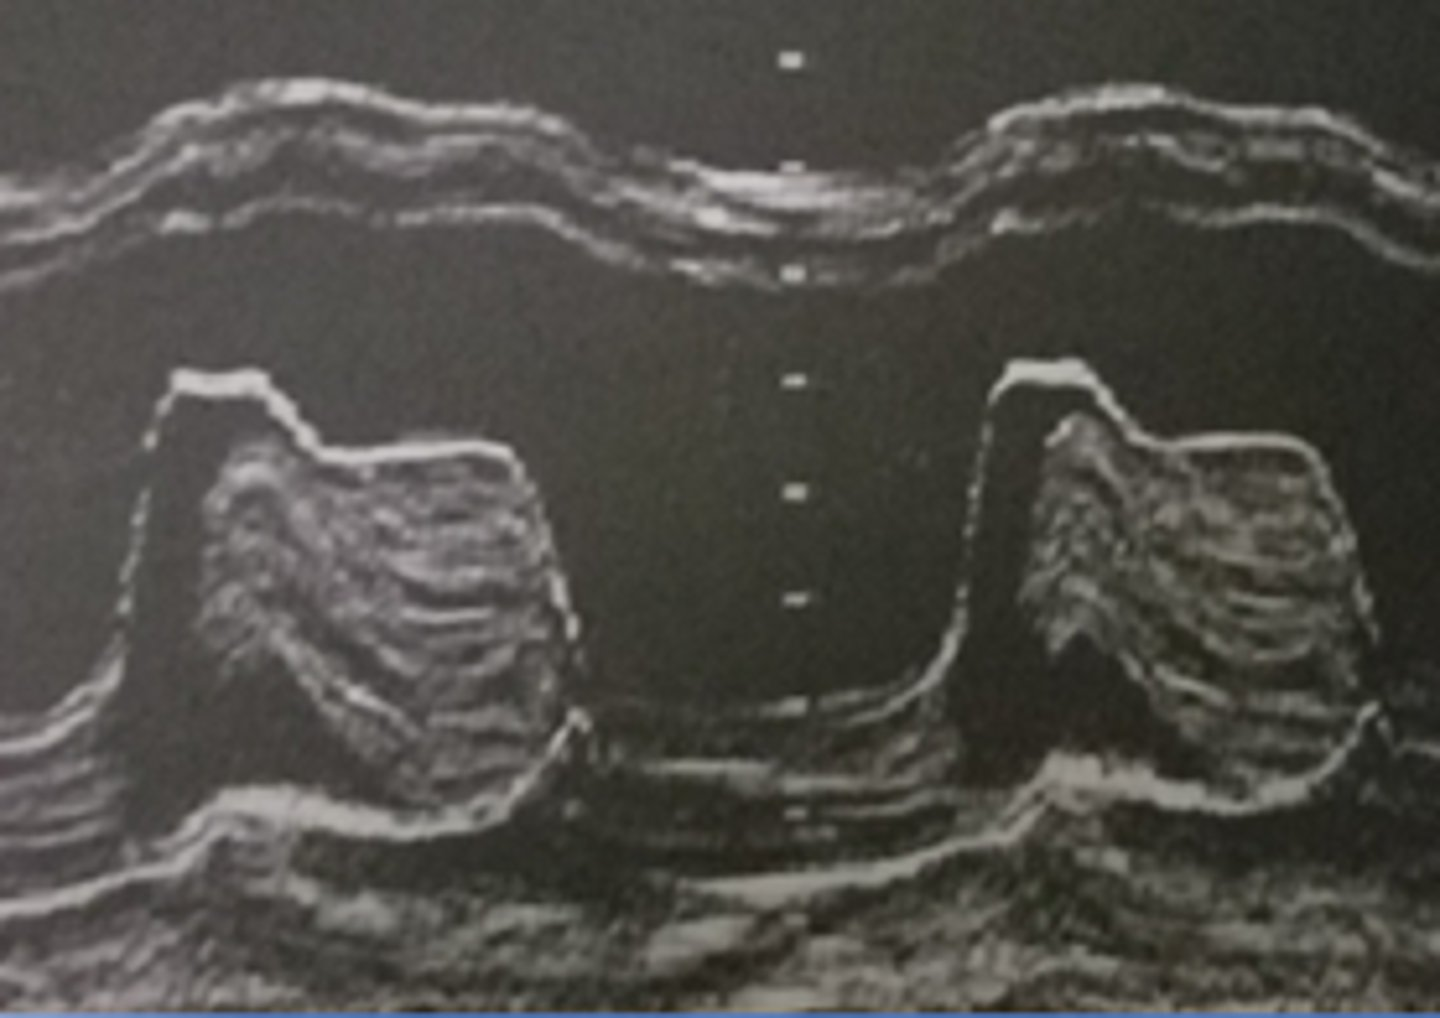

narrowing of the MV orifice with bright band of echoes in 2D and M-mode; thickening of AML and PML with anterior motion of PML; LA dilation and increased pressure; hockey puck appearance; decreased E-F slope and D-E excursion with diastolic doming

mitral valve stenosis

D-E excursion

rapid diastolic opening (1.8-2.8cm)

E-F slope

motion of AML during diastole (70-150mm/s)